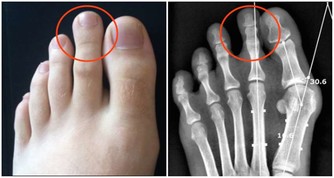

另從中醫的觀點來看,過貓菜也是很好的健康菜。黃慧娟中醫師表示,過貓屬於蕨類蔬菜,屬性偏寒,入大小腸經,具有清熱解毒和利尿的功效,可用於治療痔瘡和因細菌感染引發的腹瀉。不建議生食或直接榨汁來喝,以免對腸胃造成負擔;最好熟食或是汆燙後再吃,料理時最好搭配薑片或薑絲,可中和寒性。另,腸胃功能差或虛冷體質的人,不適合食用。